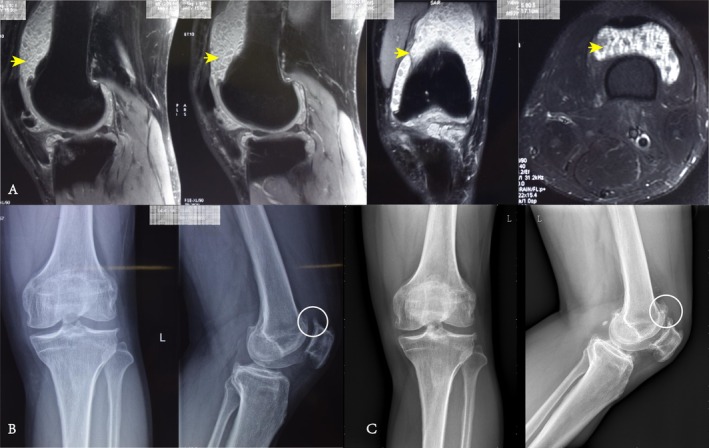

目的:滑膜软骨瘤病是一种非常罕见的良性疾病,主要发生在膝关节,可导致疼痛,活动受限,并可能对关节和软骨造成不可逆的损伤。尽管关节镜技术在滑膜软骨瘤病的手术治疗中得到了应用,但对其疗效的长期评估仍然缺乏。本研究的主要目的包括:(i)调查膝关节滑膜软骨瘤病患者关节镜手术的长期疗效;(ii)确定影响患者术后功能改善的因素。方法:我们对2009年6月至2020年1月在我院接受关节镜滑膜切除术和松体切除术的所有膝关节滑膜软骨瘤病患者进行了回顾性分析。所有病例随访时间均超过5年。资料收集包括人口学资料、临床疗效指标(VAS、oos、WOMAC等)、影像学表现、患者对手术结果的主观满意度。数据分析选择基于正态性检验结果的t检验、方差分析、非参数检验和相关方法。结果:共入组13例患者,男4例,女9例,平均随访时间113.15±30.45个月(61 ~ 145个月)。所有患者均无术后并发症、复发、恶性转化,且所有患者在随访3个月、6个月、1年、5年及末次随访时VAS评分、oos评分、WOMAC评分、Lysholm评分均有显著改善(p)。结论:本回顾性研究表明关节镜下治疗膝关节滑膜软骨瘤病是有效、安全的。它可导致干预后症状和功能的立即改善,并具有持续的长期益处。

Objective: The synovial chondromatosis is an exceptionally rare benign condition, predominantly found in the knee joint, and can result in pain, restricted mobility, and potential irreversible damage to the joint and cartilage. Despite the utilization of arthroscopic techniques in the surgical management of synovial chondromatosis, there remains a paucity of long-term assessment regarding its efficacy. The main objectives of this study include: (i) investigating the long-term efficacy of arthroscopic surgery in patients with knee synovial chondromatosis;(ii) identifying factors influencing functional improvement in patients post-surgery function.

Methods: We conducted a retrospective analysis of all patients with synovial chondromatosis of the knee who underwent arthroscopic synovectomy and loose body removal at our institution between June 2009 and January 2020. The follow-up period for all cases exceeded 5 years. Data collection included demographic details, clinical efficacy indicators(VAS, KOOS, WOMAC, etc.), imaging findings, and subjective satisfaction of patients with surgical outcomes. Data analysis selected t-tests, ANOVA, non-parametric tests, and correlation methods based on normality test results.

Results: We enrolled a total of 13 patients, including 4 men and 9 women, with a mean follow-up of 113.15 ± 30.45 months (range 61-145). There were no postoperative complications, recurrence, or malignant transformation in all patients, and the VAS scores, KOOS scores, WOMAC scores, and Lysholm scores of all patients were significantly improved at 3 months, 6 months, 1 year, 5 years, and the last follow-up (p < 0.05). However, one patient experienced osteoarthritis progression, necessitating arthroplasty.

Conclusion: This retrospective study demonstrated that arthroscopic treatment for knee synovial chondromatosis is effective and safe. It leads to immediate post-intervention improvement in symptoms and function, with sustained long-term benefits.